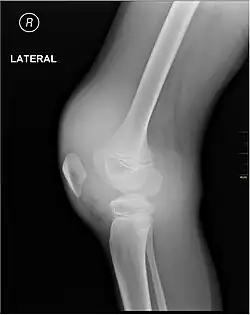

X-ray of Hemarthrosis

-